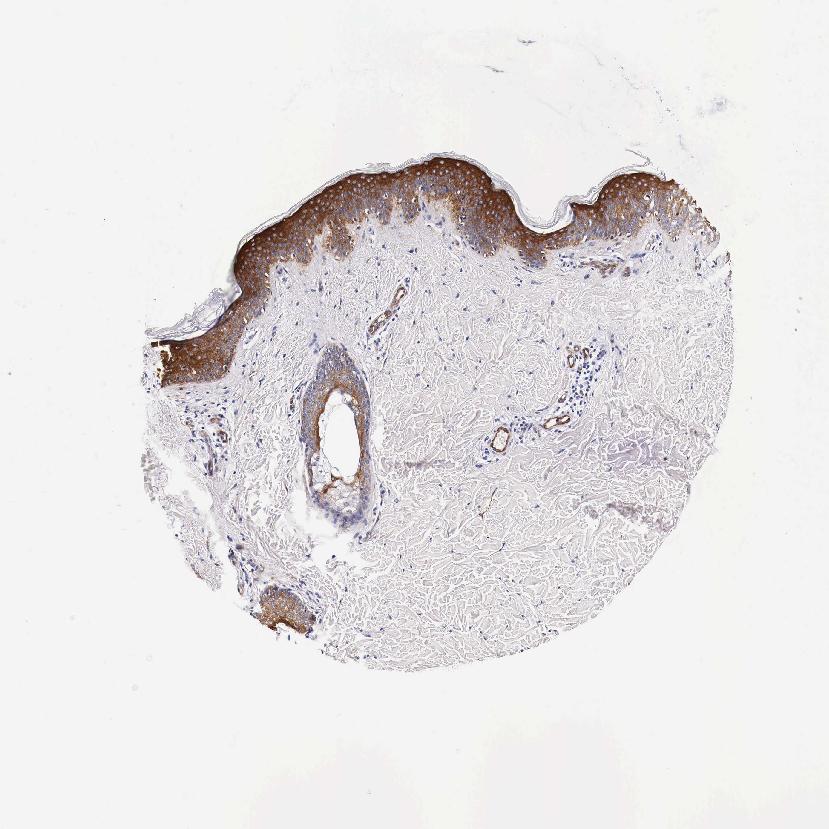

SKIN 2 - Antibody stainingi

Antibody staining in the annotated cell types in the current human tissue is reported as not detected, low, medium, or high, based on conventional immunohistochemistry profiling in selected tissues. This score is based on the combination of the staining intensity and fraction of stained cells.

Each image is clickable and will lead to virtual microscopy that enables deeper exploration of all samples and also displays staining intensity scores, fraction scores and subcellular localization as well as patient and tissue information for each sample.

Antibody HPA000497Antibody CAB004439Antibody CAB047331

Cells in basal layer --Medium

Cells in corneal layer --Not detected

Cells in granular layer --High

Cells in spinous layer --High

Endothelial cells --Medium

Epidermal cells HighHigh-

Extracellular matrix --Not detected

Fibrohistiocytic cells --Not detected

Langerhans cells --High

Lymphocytes --Not detected

Melanocytes --Medium

Vascular mural cells --Not detected